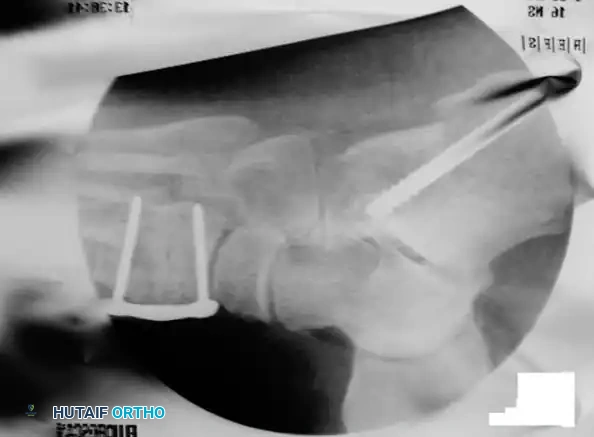

3. Posterior Calcaneal Displacement Osteotomy (Koutsogiannis)

This extra-articular osteotomy shifts the mechanical axis of the hindfoot medially, converting the Achilles tendon from an evertor to an invertor of the heel.

* Approach: Make an oblique lateral incision posterior to the peroneal tendons, avoiding the sural nerve.

* Osteotomy: Use an oscillating saw to make an oblique cut through the calcaneal tuberosity, angled at 45 degrees to the plantar surface.

* Translation: Free the medial periosteal attachments slightly to allow mobility. Translate the posterior tuberosity fragment medially by 10 to 15 mm (approximately 50% of the calcaneal width).

- Fixation: Provisionally pin the fragment with a Kirschner wire. Confirm the medial shift and overall hindfoot alignment clinically and fluoroscopically. Fix the osteotomy rigidly with one or two large-fragment (6.5 mm or 7.3 mm) cannulated headless or headed compression screws directed from the posterior heel into the anterior calcaneal body.